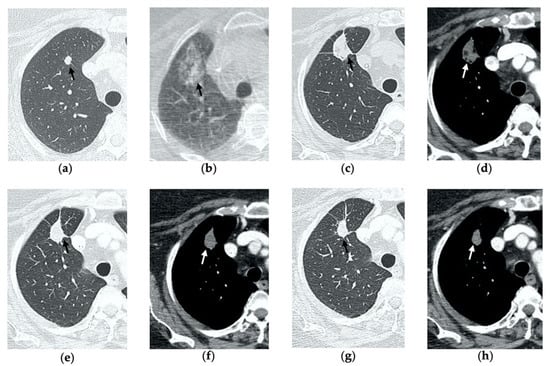

Figure 1. 74-year-old man with a pulmonary metastasis from bladder urothelial carcinoma. (a) Cone-beam CT image of the left upper lobe metastasis (black arrow) prior MWA. (b) Cone-beam CT image obtained post-procedure shows hazy GGO of the ablation site surrounding the treated nodule (black arrow) and a small layer of lateral pneumothorax (arrowhead). (c) Axial 1-month follow-up CT image shows a large consolidation with inner cavitation (black arrow). (d,e) Axial 3-month follow-up CT image shows resolution of the cavitation and decrease in size of the consolidation (black arrow) (d) and demonstrates peripheral mild enhancement with no central contrast material uptake (white arrow) (eg). Axial (f) and coronal (g) CT images obtained after 10 months show a residual fibrotic band (black arrow).

3.2. Contrast-Enhanced CT at 1 Month

By the first month after MWA, the rim of parenchymal GGO has dissolved in most patients as a result of regressing parenchymal edema, inflammation and hemorrhage, and the ablation site appears as an area of consolidation with a mean diameter still larger than the preablation zone (Figure 3c,d and Figure 4c,d) [21]. It is, therefore, crucial in this phase to measure the area of consolidation by its maximum axial diameter in order to thoroughly compare it during the following phases [7]. The consolidation may demonstrate inner cavitation or a central hypoattenuating area with reduction in contrast material uptake, along with a mild peripheral enhancement layer as an expression of reactive hyperemia, which should present smooth with linear margins (Figure 1c) [7,15]. This phenomenon must be referred to benign periablational enhancement and it should be differentiated from pathological contrast uptake, which is usually more irregular and nodular-shaped [7]. It is, therefore, pivotal to perform CT before and after contrast material administration in order to adequately evaluate the enhancement features of the treated tumor. The ablation site may also show hypoattenuating bubbles or a cavity with thin walls, containing solid tissue with reduced contrast enhancement, necrotic material or air-fluid levels, and a communication between the cavitation and a bronchus may be recognized (Figure 2c–e) [7,16]. The latter being a common finding since the necrotic tissue may be evacuated through a bronchus and it should not be mistaken for rare although possible complications, such as an abscess or a broncho-pleural fistula (BPF). Unlike the normal cavitary changes of the ablation area, an abscess is a rare complication (0.5%) [20] and appears as a cavity with thick walls, irregular internal contours and air-fluid level, and must be suspected when fever and laboratory signs of infection are present [22]. Pleural changes are also common findings, especially in peripheral lesions, including pleural thickening in the region of pleura traversed by the microwave antenna, pleural retraction and effusion [15]. Reactive mediastinal lymphadenopathy often occurs at an early stage, and it should not be considered a sign of tumor progression [7,23].

3.3. Contrast-Enhanced CT at 3 Months

On CT images obtained at 3-month follow-up, the size of the ablation zone should be the same or still larger than the baseline tumor, although it undergoes further involution compared to the early phase, as during the fibrosis process the wall thickness and the previously depicted cavities progressively decrease (Figure 1d) [7]. The attenuation of the ablated tissue decreases, as there is no more central contrast material uptake in relation to the local necrotic changes, while the peripheral benign enhancement may persist or decrease (Figure 1e). Overall, the size of the ablation area at this stage should become stable along with a decrease in wall thickness [7,8].

3.4. Contrast-Enhanced CT at 6 Months

After 6 months, the ablation site undergoes further involution and there should not be any inner contrast enhancement, except for the persistent benign periablational area (Figure 2f,g) [7]. The previously mentioned cavities decrease in size and may completely disappear. CT images may show fibrotic scarring without contrast enhancement and mild architectural parenchymal distortion of the surrounding lung (Figure 1f,g) [24]. At this stage, small treated nodules may already show a linear fibrotic evolution on CT images (Figure 2h,i).